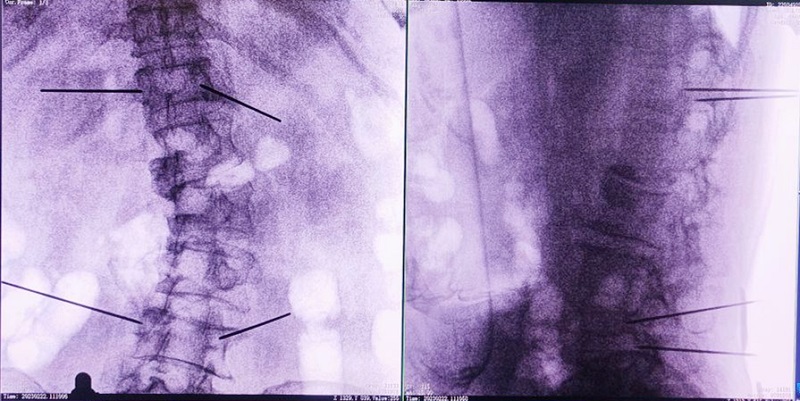

机器人辅助下椎体成形术,是以手术机器人智能机械臂为基础,仿照经皮骨水泥椎体成形术的施术步骤,限定穿刺点、穿刺方向、角度和深度,使穿刺针经过安全路径进入目标区域,然后进行骨水泥注入,辅助手术设计、精准指导手术实施。以普爱医疗的骨科手术机器人PL300B为例,其辅助进行的一例胸腰椎压缩性骨折经皮椎体成形术的过程如下:

(3)根据设定好的的位置和入针方向,植入引导针;

(4)所有引导针植入完毕后,沿引导针方向进行椎弓根及椎体置管,建立通道;

(5)沿通道注入骨水泥,恢复椎体高度,并观察其扩散情况,达到满意效果后,停止注入骨水泥。